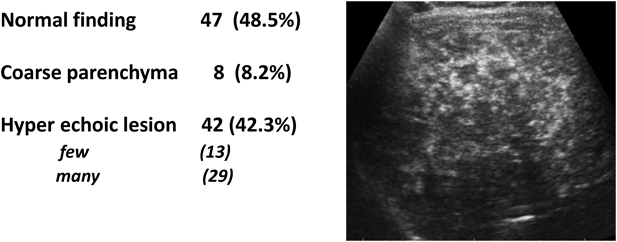

Fontan術後に生じる急性および慢性の肝構造異常および肝機能障害はFontan associated liver disease(FALD)と呼ばれ,近年大きな注目を集めている.慢性的な静脈圧の上昇と低心拍出が大きく影響していると考えられる.成人に達したFontan患者241例の検討(年令中央値25.8歳,術後経過中央値20.3年)ではほとんどの患者で様々な程度の肝線維化が見られ,約1/3の症例で肝硬変が見られ20),最終的に肝がんの発生素地になり得る21).腹部超音波検査での異常所見は不均一な肝実質所見や単発または多発性のhyper-echoic lesion(Fig. 2)がFontan術後遠隔期の患者の多くで認められ22),肝生検では類洞拡張,小葉中心性壊死,門脈線維化などの所見が特徴的である23).心臓カテーテル検査および一般の血清生化学検査,また血清線維化マーカーと画像所見,生検所見は必ずしも相関しない.FALDはFontan術後年数とともに増加し,現在のところFALDのスクリーニングと診断,治療法は確立されておらず予後の予測も困難である.そのためFALDを伴ったfailing Fontan患者の心移植の適応基準については明確なものがない21).またFontan術後患者の肝障害の指標として血漿クレアチニンとビリルビンによるModel for End Stage Liver Disease excluding INR(MELD-IX)やVAS score(varices, ascites, splenomegaly)などが予後と相関すると言われている24, 25)

Fig. 2 Liver ultrasound findings in 97 patients after >10 years of follow-up after surgery in Fukuoka Children’s Hospital